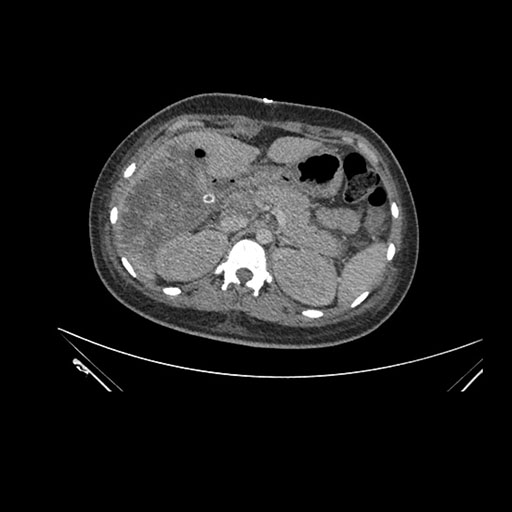

Imaging Analysis

Look through the patient's CT scan to identify any areas of concern for the necessary procedure.

Coronal Arterial

Based on initial findings, which issue(s) would you be most concerned about?